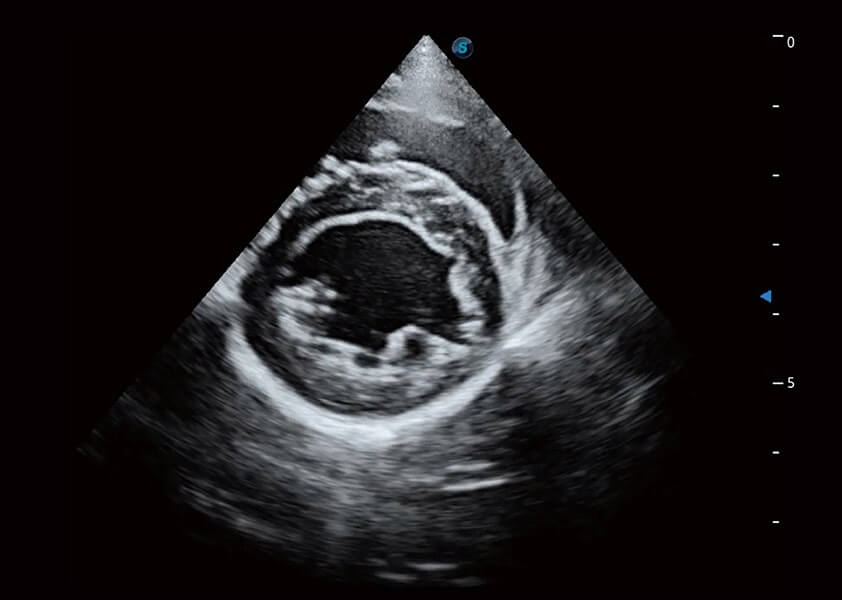

ProPet 60 作为一款高端台式动物超声设备,为动物医生的日常诊断提供了一系列贴合动物临床需求、解决临床实际问题的高级成像功能。凭借全系列高清探头,满足医生对腹部、心脏、生殖、浅表、肌骨等成像的所有需求,切实帮助您提升检查效率,提高诊断信心。

动物是人类最亲密的朋友和最值得信赖的伙伴。竞技宝(JJB)官方网站也一直致力于探索动物专用的超声影像解决方案。 全新推出的ProPet系列,是竞技宝(JJB)官方网站在动物超声影像智能化、专业化、精准化的一次跨越式革新。动物不能用言语来表述自己的不适,通过超声影像,ProPet系列搭建了动物医生与不同物种沟通的“桥梁”,为动物医生注入了“治愈之力”。